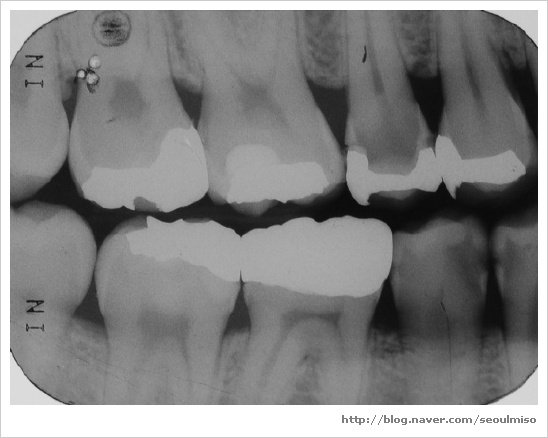

치아 사이의 충치를 제대로 확인하려면 교익 방사선 사진이 필요합니다.

( 추가: 파노라마 사진, 교익 방사선 사진 )

파노라마